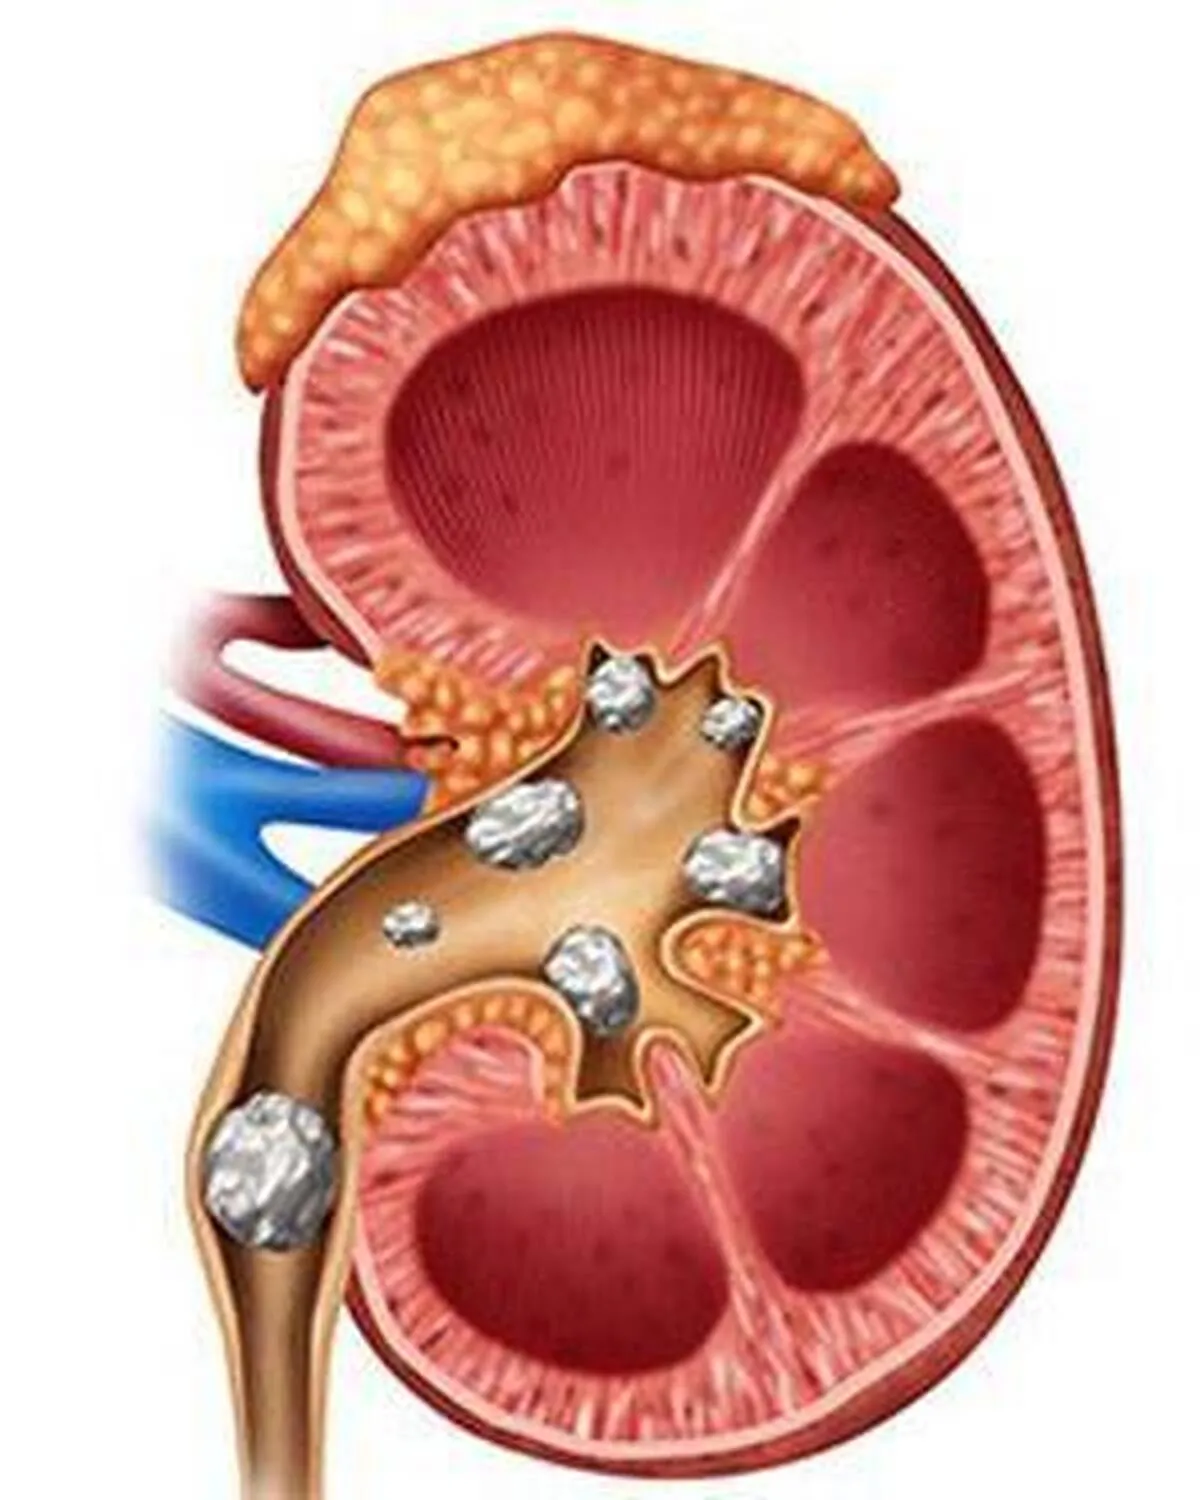

به گزارش صراط به نقل از تابناک، سنگهای کلیه رسوباتی سخت از جنس مواد معدنی (کلسیم، اگزالات و فسفات) هستند که در کلیههای شما تشکیل میشوند. ابتلا به سنگ کلیه دلایل زیادی دارد و میتواند هر بخشی از دستگاه ادراری شما از کلیهها تا مثانه را درگیر کند و دفع این سنگها اغلب بسیار دردناک است. بسته به وضعیت بیمار، ممکن است نیاز به مصرف داروهای ضد درد وجود داشته باشد. نوشیدن آب زیاد برای دفع سنگ کلیه ضروری به نظر میرسد. درد شدید در پهلو، دردی که به قسمت تحتانی شکم و کشاله ران کشیده میشود، درد در هنگام ادرار، حالت تهوع و استفراغ، نیاز مداوم به ادرار کردن، تب و لرز (در صورت وجود عفونت)، از علائم ابتلا به سنگ کلیه هستند.